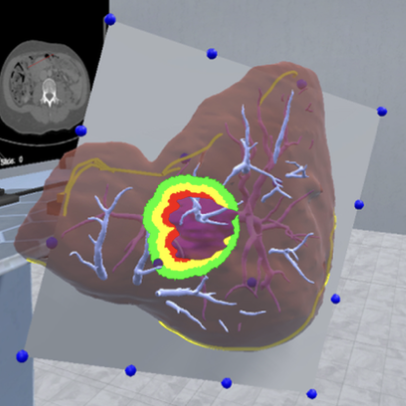

Chheang, V; Schott, D; Saalfeld, P; Vradelis, L; Huber, T; Huettl, F; Lang, H; Preim, B; Hansen, C

Advanced liver surgery training in collaborative VR environments Journal Article

@article{chheang_advanced_2024,

title = {Advanced liver surgery training in collaborative VR environments},

author = {V Chheang and D Schott and P Saalfeld and L Vradelis and T Huber and F Huettl and H Lang and B Preim and C Hansen},

url = {https://www.sciencedirect.com/science/article/pii/S0097849324000050},

doi = {10.1016/j.cag.2024.01.006},

issn = {0097-8493},

year = {2024},

date = {2024-04-01},

urldate = {2024-04-01},

journal = {Computers & Graphics},

volume = {119},

pages = {103879},

abstract = {Virtual surgical training systems are crucial for enabling mental preparation, supporting decision-making, and improving surgical skills. Many virtual surgical training environments focus only on training for a specific medical skill and take place in a single virtual room. However, surgical education and training include the planning of procedures as well as interventions in the operating room context. Moreover, collaboration among surgeons and other medical professionals is only applicable to a limited extent. This work presents a collaborative VR environment similar to a virtual teaching hospital to support surgical training and interprofessional collaboration in a co-located or remote environment. The environment supports photo-realistic avatars and scenarios ranging from planning to training procedures in the virtual operating room. It includes a lobby, a virtual surgical planning room with four surgical planning stations, laparoscopic liver surgery training with the integration of laparoscopic surgical instruments, and medical training scenarios for interprofessional team training in a virtual operating room. Each component was evaluated by domain experts as well as in a series of user studies, providing insights on usability, usefulness, and potential research directions. The proposed environment may serve as a foundation for future medical training simulators.},

keywords = {},

pubstate = {published},

tppubtype = {article}